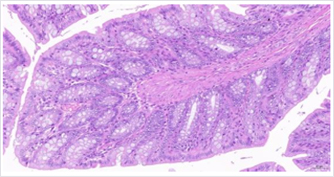

与模型组比较,中和高剂量后生元组,粘膜层肠上皮结构基本完整,上皮细胞脱落和固有层与粘膜下层的水肿较少,未见明显炎症。